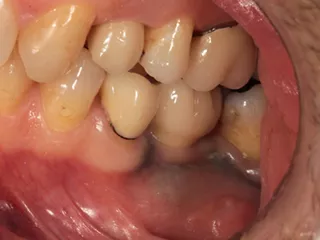

CASE No.1 奈良 嘉峰 先生(神奈川県茅ヶ崎市開業)

Labrida 施 術 前

施 術 前 (レントゲン写真)

Labrida 施 術 後(4週後 )

炎症とBOP消失

施 術 後 (レントゲン写真)